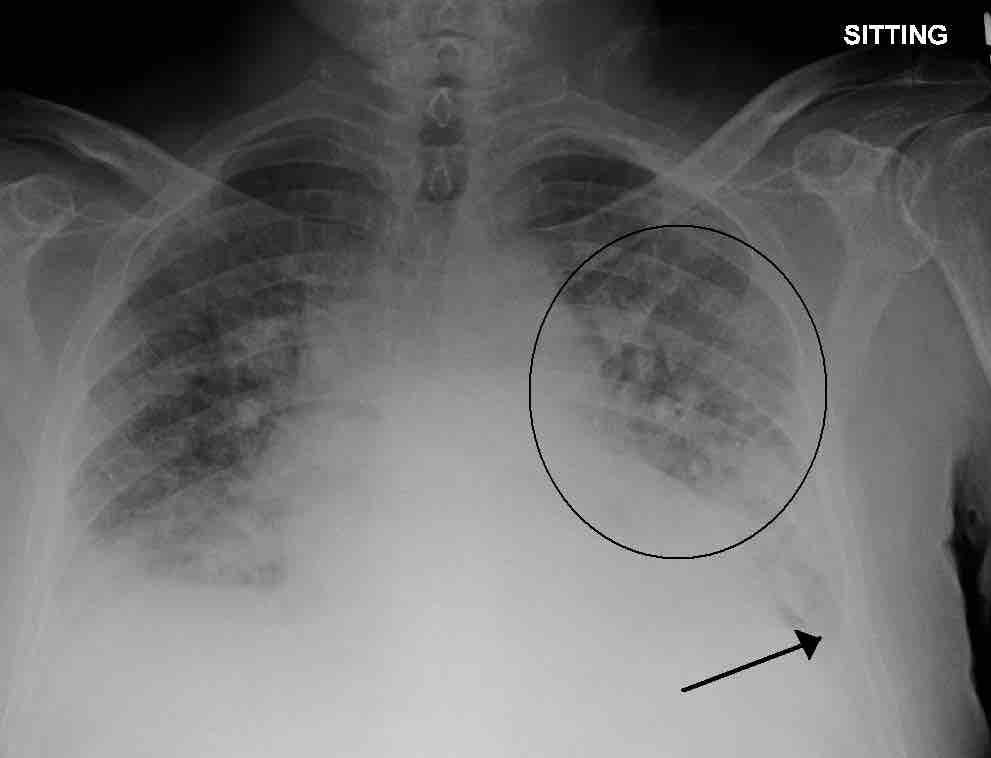

Dead Space: V/Q Mismatch

A physiological shunt can develop if there is infection or edema in the lung which decreases ventilation, but does not affect perfusion; thus, the ventilation/perfusion ratio is affected. Pulmonary edema with small pleural effusions on both sides (as shown) can cause changes in the V/Q ratio.